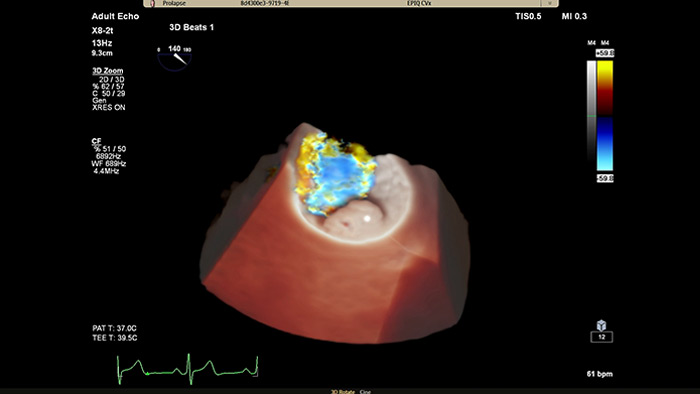

Verbesserte Darstellung von Strukturen und Blutfluss mit TrueVue Color